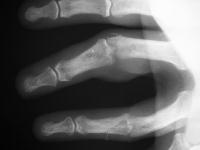

These are before and after radiographs of middle and ring proximal interphalangeal joints in a young man after a rotating blade injury resulting in dorsal bone and soft tissue loss. Initially treated elsewhere with K wire fixation, ring finger skin graft and abdominal flap reconstruction of the middle finger, he presented with instability, stiffness, pain and lateral angulation. Surgery was technically difficult because normal landmarks were distorted or missig. Despite complex bone and soft tissue loss,  stability was rendered in part by the restoration of concentric joint surfaces.

Correction of alignment.

Click for larger image